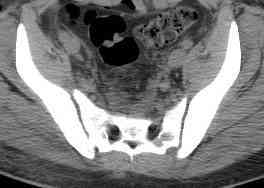

Уважаемые коллеги! опять вопрос по повреждению таза. Больной получил производственную травму 10 дней назад - удар балкой около 3 тонн в область верхней трети правого бедра и лона.

Был диагностирован перелом "типа бабочки" и повреждение уретры. Сделана цистостома. У насв отделении 3 дня. Имеется огромная флюктуирующая гематома с "галифе"-образной деформацией обеих бедер. Пнкционно эвакуировали в несколько приемов из подфасциальных полостей на бедрах около 3 литров геморрагического отделяемого с последующей эластической компрессией. При пункциях выявлено сообщение полостей на бедрах - видимо через поравннуюдиафрагму дна и полость таза - при удалении крови справа уменьшался объем левого бедра. Какой то активности проявялять покабоимся - аппаратная фиксация через отслоенные ткани представляется чреватой нагноением, открытая фиксация в условиях такой гематомы тоже не радует. Хотелось бы услышать ваше мнение

можно полечить в 2 этапа:как правило в области гребней гематомы все же не бывает, если гребни "свободны", то можно ограничиться на первом этапе передней рамой, вводя стержни через них (повреждение ротационно-нестабильное), затем после лечения отслаивающего повреждения Morel-Lavallee, выполнить открытую репозицию, внутреннюю фиксацию, возможно вместе с урологами. Тактику возможного лечения этой

Типичная картина Morel-Lavallee повреждения.

Безуспешны многочисленные шприцевые эвакуации, мы лечим в операционной, доступом на латеральной поверхности, открытием образования с удалением и очисткой полости щеткой. Закрываем с дренажной трубкой (в архивах сайта) и накладывается мягкая повязка Спика из нескольких слоев эластичной повязки.

Следующим этапом через 5-6 дней приступаем к фиксацию повреждения таза, иначе прооперериванные на фоне Morel-Lavallee повреждения осложняются инфицированием послеоперационной раны.

18.12. - отдельное спасибо еще раз А.В.Рункову- больного оперировали (А.В.Рунков) - произведен остеосинтез аппаратом - фиксация за крылья, два стержня в лонные кости и репозиция (почти полная) снимки будут чуть позже.

Дренировали отслойки на бедрах с их санацией. В правой ягодичной области сформировалась зона некроза. Больной "подвешен" за аппарат.